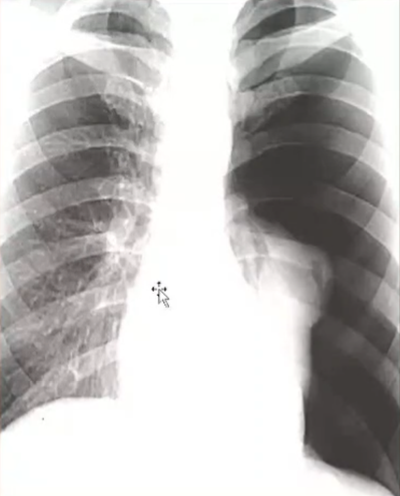

Rx toracică, incidență P-A

DESCRIERE:

DX: atelectazie prin NBP central endobronșic (pe bronhia principală stg)

DD: pleurezie masivă → caracter expansiv

la niv. întregului hemitorace stg → opacitate extinsă, nesistematizată, de intensitate mare, omogenă

caracter retractil → tracționează traheea și mediastinul de partea afectată

fără bronhogramă aerică

duce la micșorarea spațiilor intercostale

la niv. hemitoracelui controlateral → hipertransparență compensatorie (emfizem)